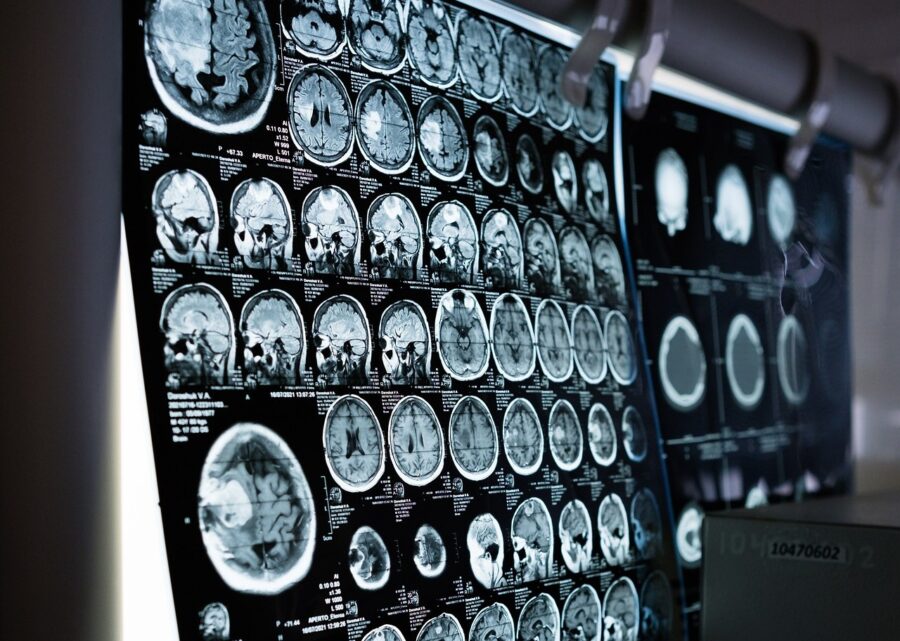

Novo istraživanje pružilo je nove uvide u mehanizme potencijalno uključene u Alzheimerovu bolest. Ta studija se fokusira na protein kontaktin-4 (CNTN4) i njegovu interakciju s amiloidnim prekursorskim proteinom (APP). Vjeruje se da CNTN4 igra ulogu u formiranju neuronske mreže, dok je APP poznat po proizvodnji amiloid-beta peptida koji se nakupljaju u mozgovima pacijenata s Alzheimerovom bolešću.

Znanstenici su proveli testove na miševima i otkrili da je interakcija između CNTN4 i APP ključna za neuralnu elongaciju, proces neophodan za rast i povezanost neurona. Istraživanje vezano za to objavljeno je u časopisu Royal Society Open Biology.

Uspostavljena veza CNTN4 s autizmom isprva je privukla znanstvenike da istraže njegove moždane funkcije i moguće veze s neurodegenerativnim bolestima. Uništavanjem gena CNTN4 u motoričkom korteksu miševa, regiji koja je neophodna za planiranje dobrovoljnog kretanja, tim je primijetio poremećenu neuralnu elongaciju i abnormalni razvoj neurona. Studija je otkrila da CNTN4 radi s APP-om kako bi regulirao taj proces.

Daljnji eksperimenti s ljudskim stanicama uzgojenim u laboratoriju otkrili su složen odnos: onemogućavanje proizvodnje CNTN4 smanjilo je razine APP-a, ali ih nije potpuno eliminiralo, što ukazuje na kompenzacijski mehanizam između dva proteina. To sjecište razvojnih i neurodegenerativnih putova nudi uzbudljive nove uvide u šire implikacije ta dva proteina, ističe Bamford.

Svako novo razumijevanje bioloških procesa povezanih s Alzheimerovom bolešću približava nas mogućim načinima liječenja ili preventivnim mjerama. Veza CNTN4-APP dodaje još jedan dio slagalici Alzheimerove bolesti, iako potpuna slika i dalje ostaje nejasna.